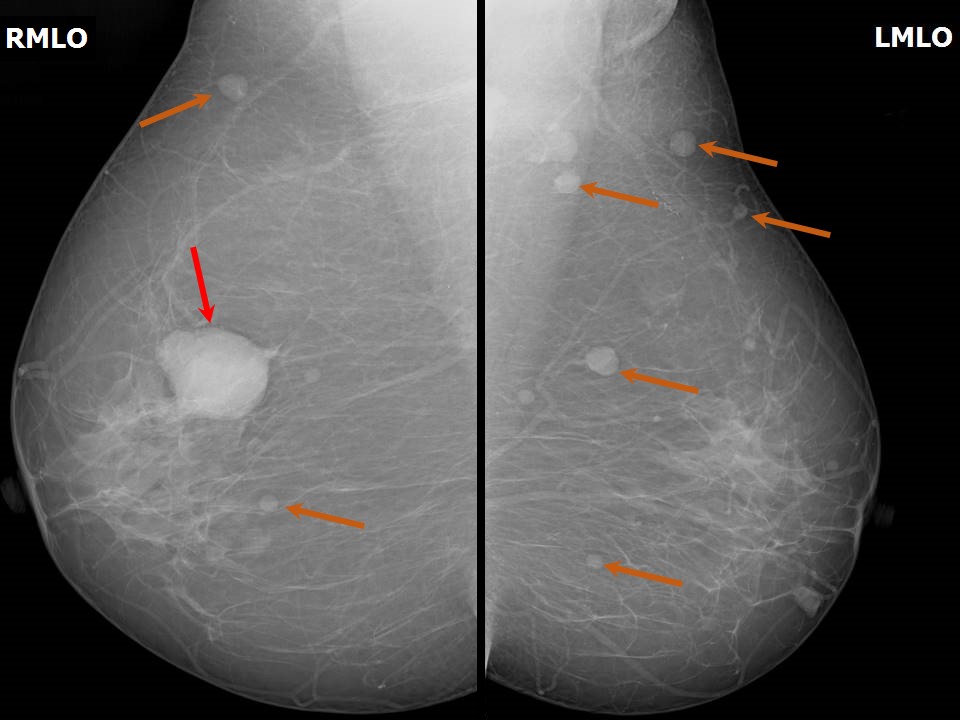

Феномен гипердиагностики в маммографии: примеры и иллюстрации

Раздел: Образы вокруг